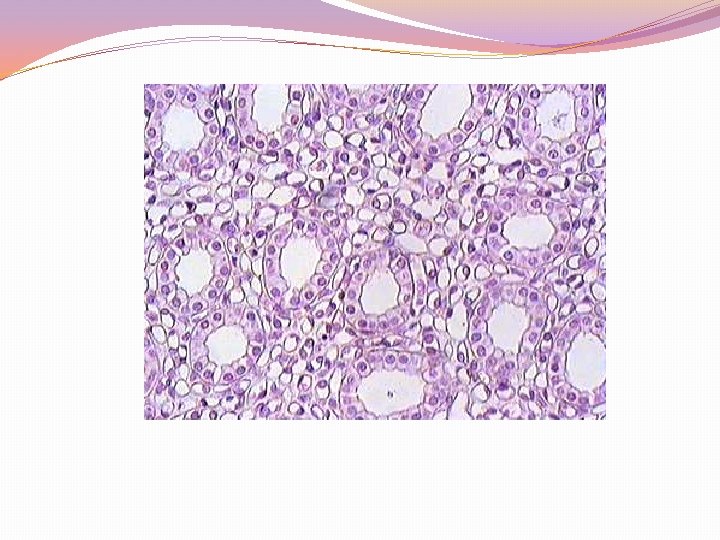

a. Glomerulus �Suatu gumpalan kapiler yang beranastomosis yg terdiri dari arteri afferen dan arteri efferen. �Diantara kapiler sering dijumpai sel mesangium (derivat mesenkim). �Daerah pingir banyak terdapat sel yang berasal dari kapsul bowman.

b. Kapsul bowman �Merupakan bagian nephron yang berbentuk seperti mangkok. �Rongga antara dua dinding kapsul disebut rongga kapsul, untuk menampung bahan kemih yang berfitrasi dari glomerulus. �Dinding sebelah dalam disebut epitel glomerulus, sedangkan bagian luar disebut epitel parietal. �Sel epitel glomerulus yang bertonjolan banyak itulah yang disebut podosit.

RENAL CORPUSCLE (CAPSULA BOWMAN DAN GLOMERULUS)